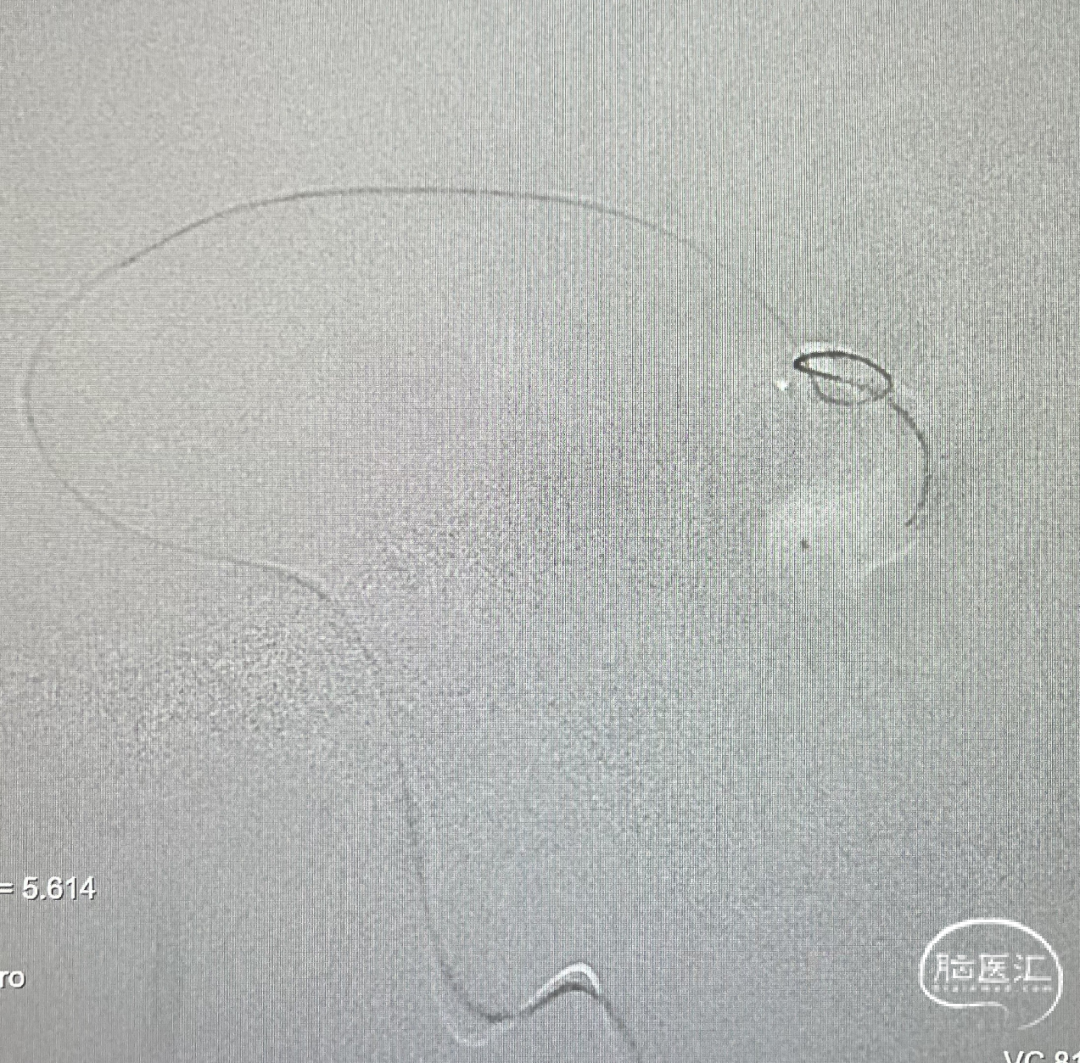

由于瘘口流量大,为了防止栓塞材料过度弥散,并逃逸至深静脉,首先通过Echelon-10微导管向静脉球内填入Feng 12/40、Feng 10/30两枚弹簧圈,限制后续液态栓塞材料仅在静脉起始部弥散。

随后回撤Echelon-10微导管,并通过Echelon-10微导管和Marathon微导管交替注入Onyx-34、Onyx-18,此时可见Onyx首先被血流冲至静脉球内,但被弹簧圈篮筐限制,并在瘘口范围内弥散。

通过“注射-停顿-再注射”,Onyx进一步在瘘口及供血动脉段和引流静脉起始部弥散满意

造影显示瘘口不显影,无静脉早显。